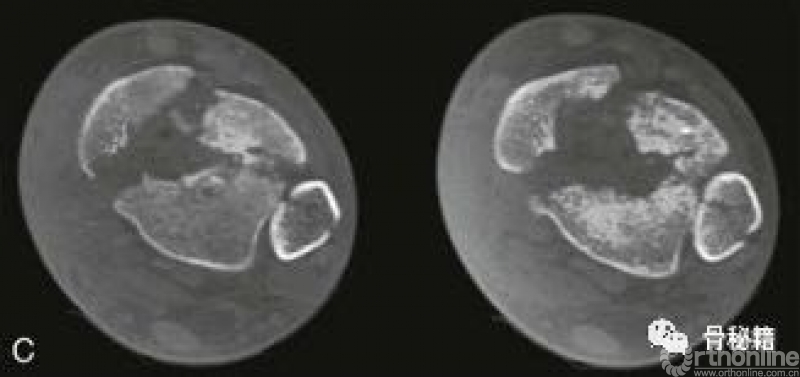

五、复杂pilon骨折的复位和内固定

A和B 腓骨钢板和跨关节外架的应用。注意关节面的压缩(箭头)。

C 前内侧切口。注意胫前肌腱(黑色箭头)和胫骨干骨折(白色箭头)。

D 关节面的复位。

E 使用克氏针复位,然后使用螺钉固定。

F 应用中和钢板。

G和H 术后轴和关节面的前后位X线片和侧位X线片。

一旦关节面重建后,应主要注意干骺端的交界处。当复位长骨骨折时,力线的对齐是主要的功能要求。与关节复位相反,干骺端重建的目标较少依赖于解剖复位,更多依赖于恢复足够的长度和旋转以及力线的对齐。这也可以通过使用外架或股骨牵引器来实现。